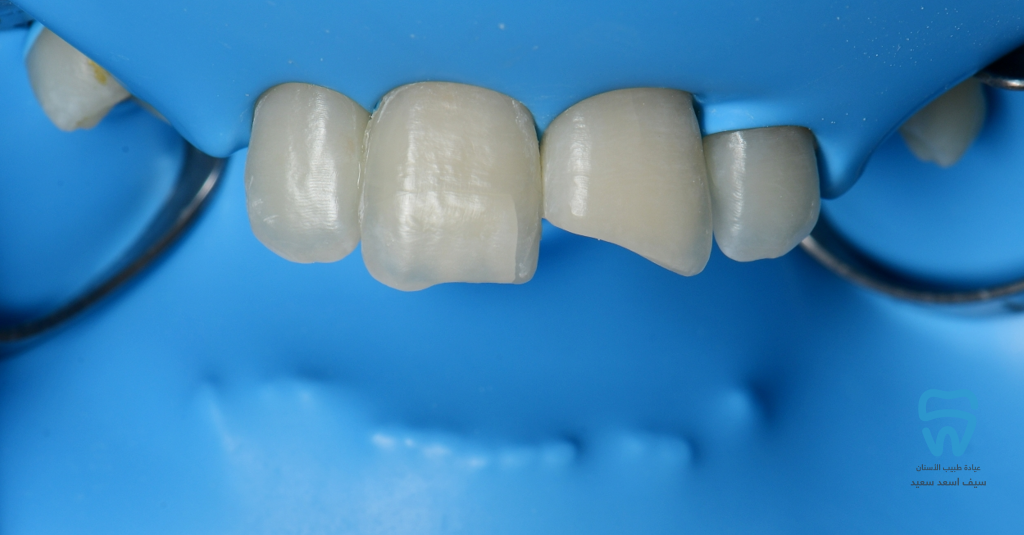

Isolation and cavity preparation